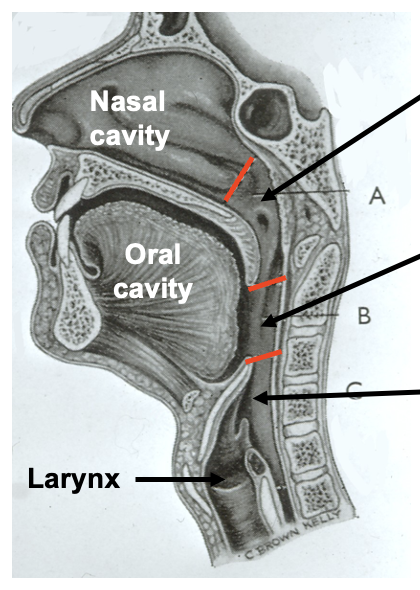

what are the divisions of the pharynx

regions of the pharynx

nasopharynx

oropharynx

laryngopharynx

oropharynx: which vertebrae is it level with posteriorly

body of the second cervical vertebrae

upper part of the third cervical vertebrae

laryngopharynx: borders

laryngopharynx

from the tip of the epiglottis

to the lower border of the cricoid cartilage

laryngopharynx: at which vertebrae is the cricoid cartilage level with

the cricoid cartilage lies at the level of C6

laryngopharynx: at which vertebrae is it level with posteriorly

the laryngopharynx extends posteriorly from the third to the sixth cervical vertebrae